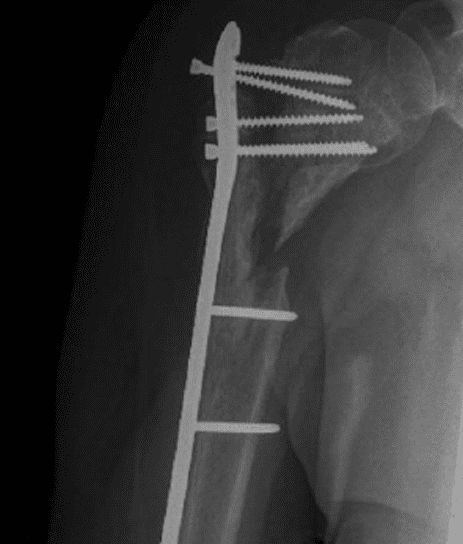

For fracture and revision treatment

The system offers a set of modular Proximal Bodies in several sizes and heights to be paired with a broad range of Modular Stems, available in different diameters and lengths as well as different surface and coating options for cemented and cementless fixation.

The Proximal Bodies’ spiked surface, together with m-l and a-p holes for suture fixation, allow for stable and physiologic tuberosities reattachment. The modular concept of the fracture components supports the surgeon in achieving adequate joint restoration even in cases with poor anatomical landmarks.1